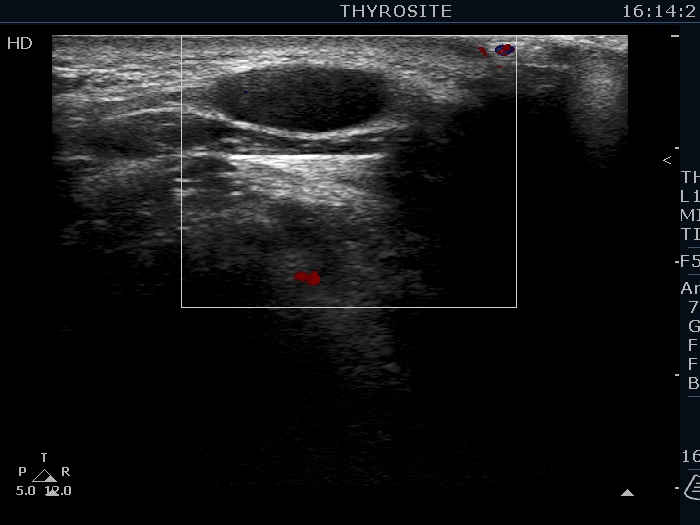

Ultrasonography. The thyroid was echonormal. There were several hypoechoic nodules in the left lobe. The middle one had back wall cystic figures. There were 3 or four discrete, deeply hypoechoic lesions above and lateral to the left lobe in the neck. One of them presented with a hilum-like figure while the others lacked hilum.

The lymph nodes had a non-typical presentation. They lacked a regular hilum.